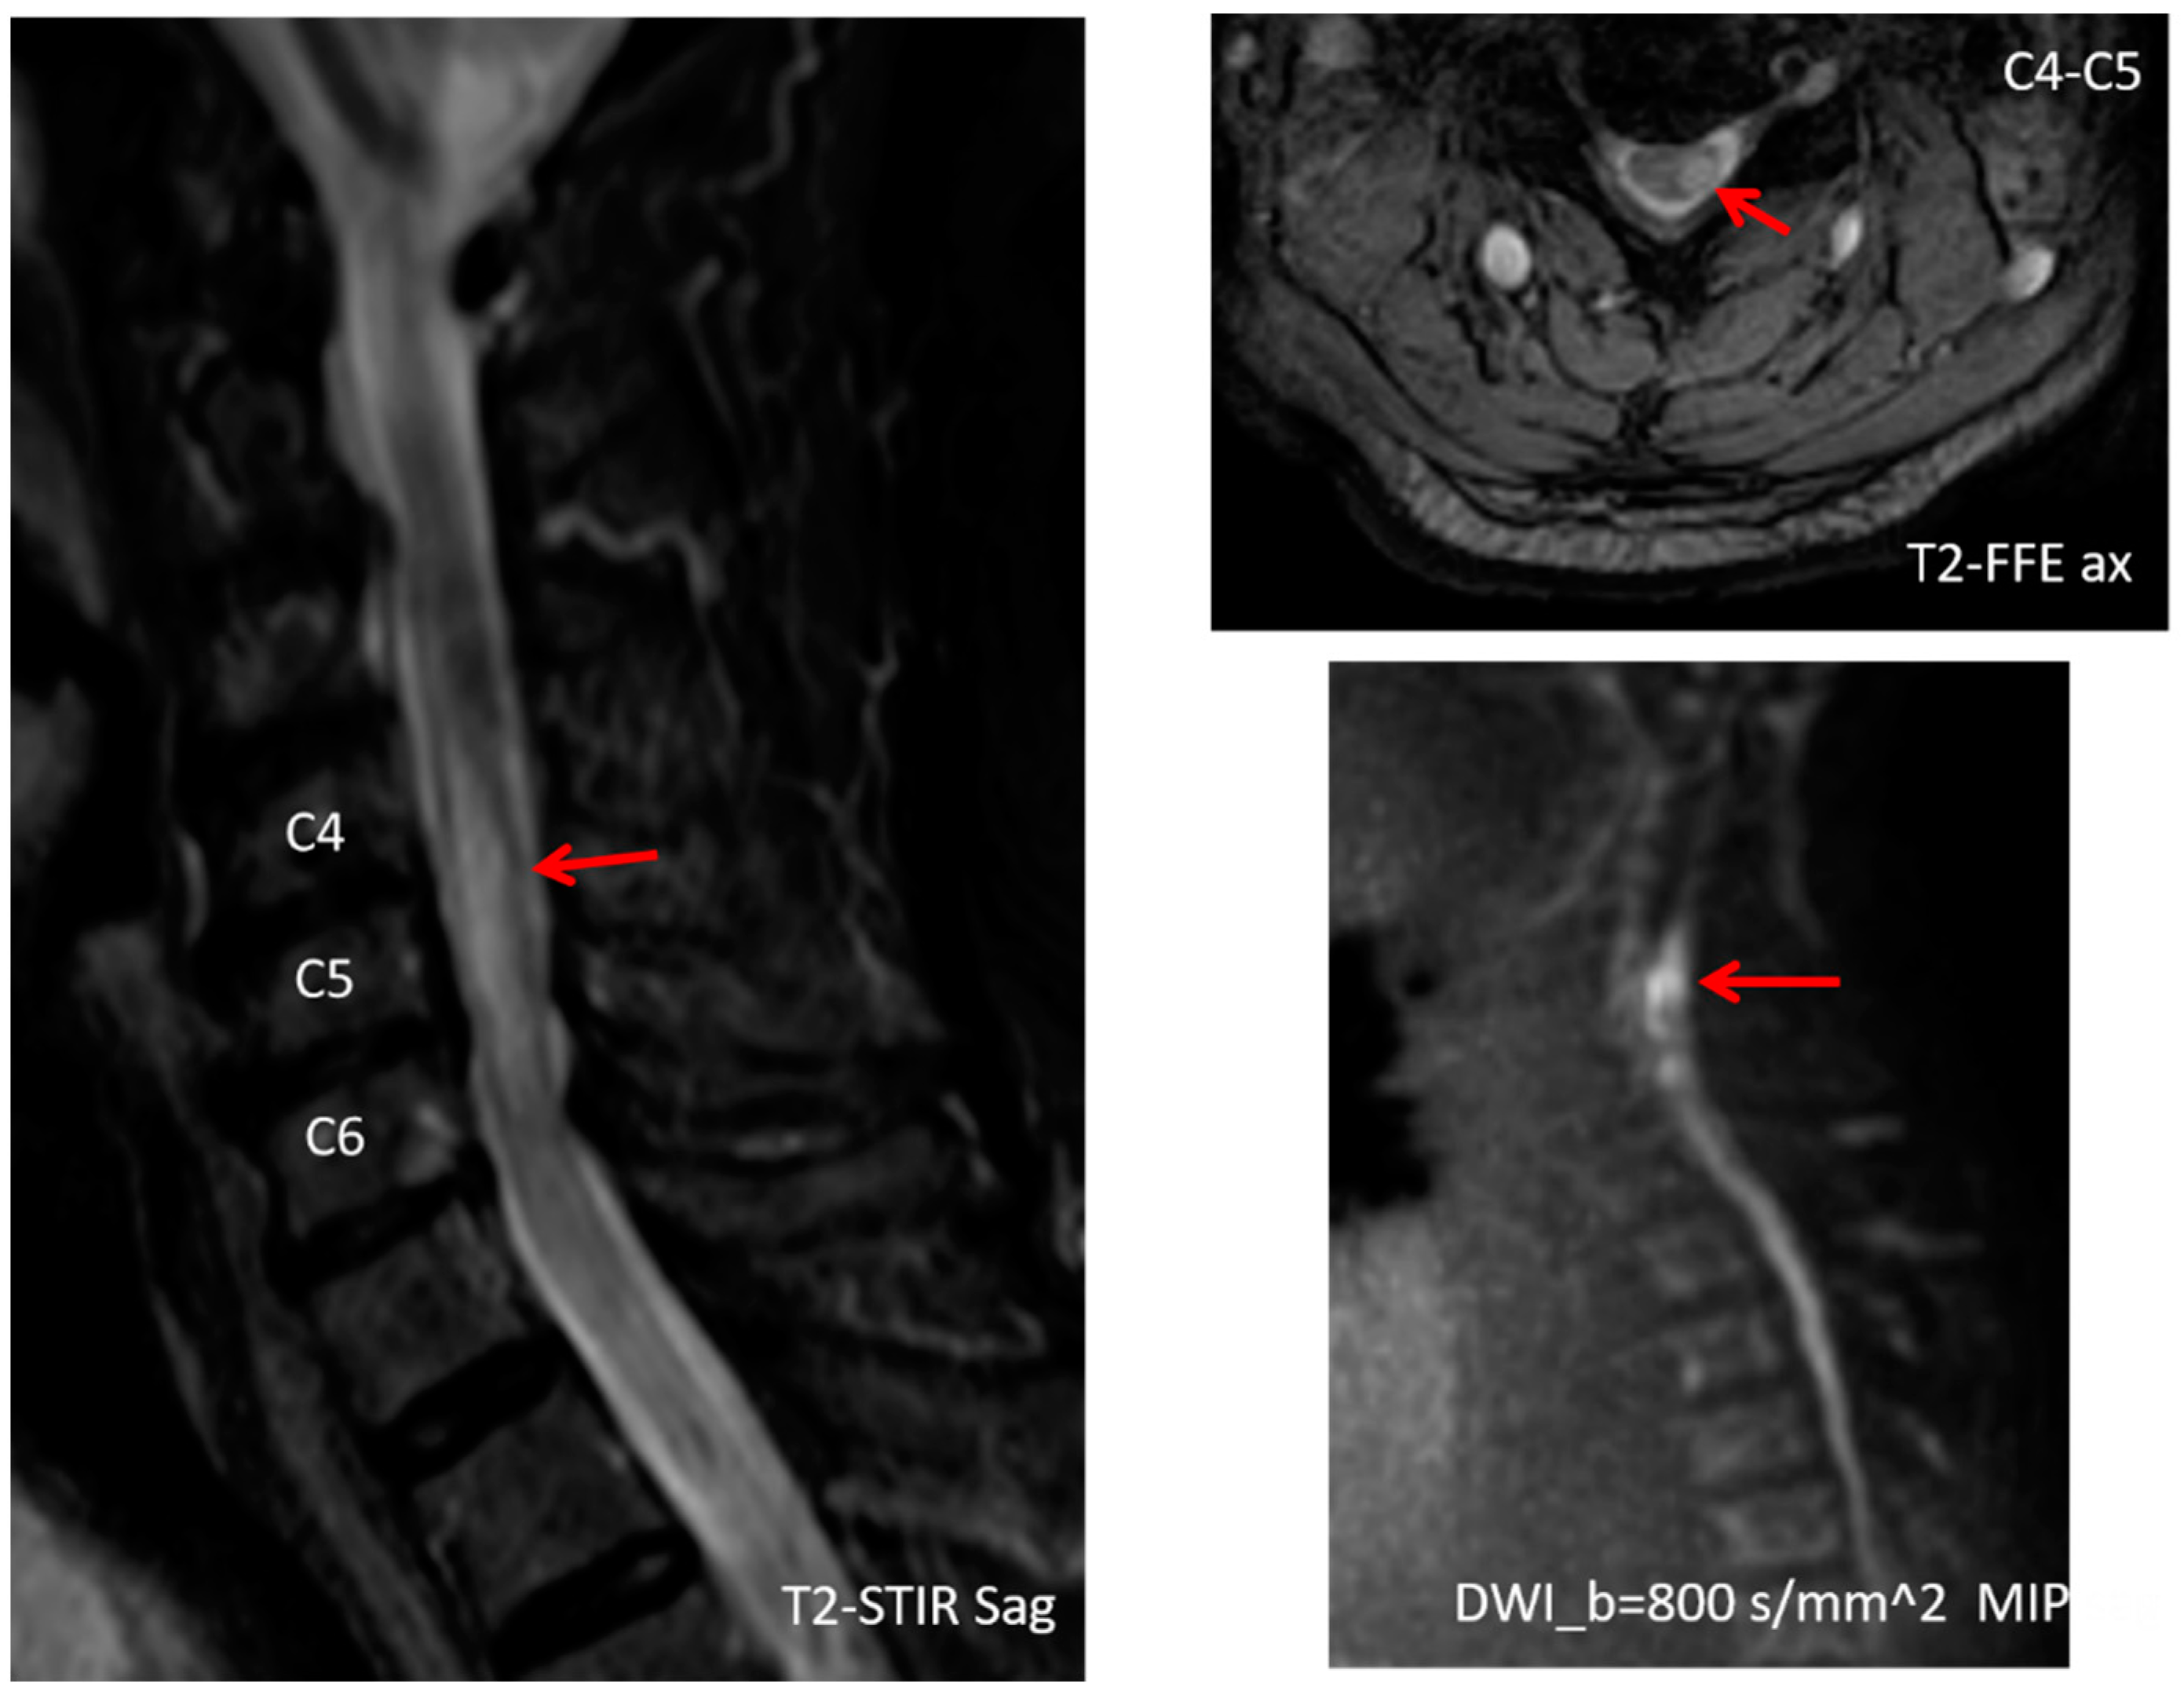

2. Case Presentation